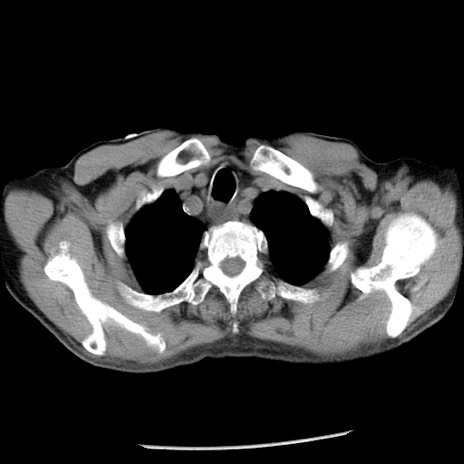

症例26(横断像)

冠状断像

【症例】80歳代男性

【主訴】嘔吐

【現病歴】昨晩2回嘔吐あり、今朝になっても嘔吐あり。来院。

【既往歴】胃潰瘍

【身体所見】意識清明、BT 37.6℃、BP 166/95mmHg、HR 100bpm、SpO2 97%、腹部:平坦・軟、腸蠕動音聴取良好、圧痛なし。

【データ】WBC 21900、CRP 1.46